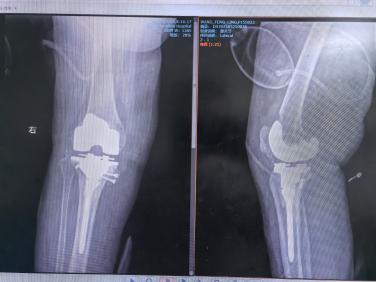

在武漢同濟(jì)醫(yī)院肖駿教授的指導(dǎo)下,通用技術(shù)湖北航天醫(yī)院骨科主任黃飛團(tuán)隊(duì)精心規(guī)劃,王女士的膝關(guān)節(jié)置換手術(shù)順利完成。考慮到她的類風(fēng)濕病史,醫(yī)生團(tuán)隊(duì)制定了個(gè)性化的手術(shù)方案,使用微創(chuàng)技術(shù)進(jìn)行精準(zhǔn)的關(guān)節(jié)置換,最大限度減少術(shù)后并發(fā)癥的風(fēng)險(xiǎn)。同時(shí),術(shù)后制定了針對(duì)性的抗炎治療和康復(fù)方案,確保她能夠順利恢復(fù)功能。

膝關(guān)節(jié)置換術(shù)后

術(shù)后僅一周,王女士便能夠借助助行器下床活動(dòng),臉上重現(xiàn)久違的笑容,生活質(zhì)量顯著提升。